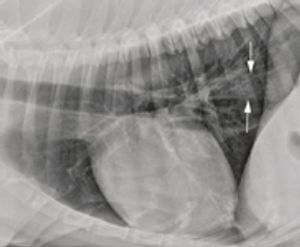

A bronchial pattern on radiographs indicates pathology involving the airways. It can be a subtle pattern to recognize, so let's look at some of the features.